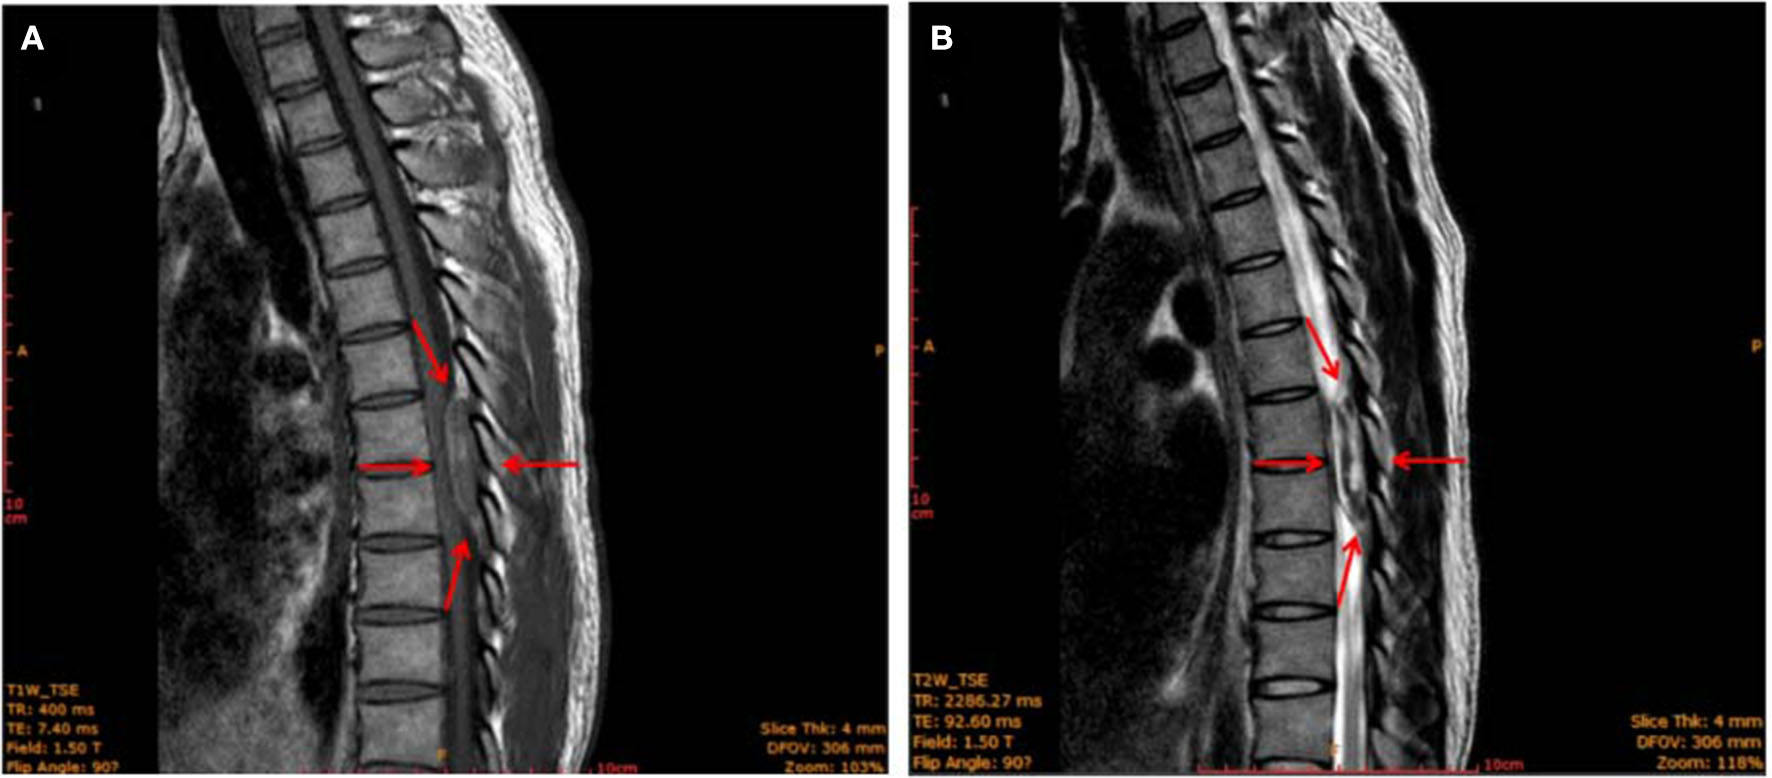

However, 4 h after epidural analgesia, the patient suddenly developed bilateral rigidity and paralysis in the lower extremities. A physical examination revealed numbness below the level of T6, grade I strength, and hyperactive deep tendon reflexes were noted in the bilateral lower extremities, while Babinski's response was also positive. The patient also reported difficulty with bowel or urinary retention or incontinence, and superficial sensations were abnormal in bilateral lower extremities. Gadolinium-enhanced magnetic resonance imaging (MRI) showed an epidural mass measuring 11 × 16 × 11 mm with a distinct border, which intensified at the T7–T8 extradural level. An iso-intense area was detected on the T1-weighted images (T1WI) and mixed-signal intensity on the T2-weighted images (T2WI). The T1-weighted transverse plane showed that the lesion occupied more than half of the T7–8 canal (Figure 1). Laminectomy, intravertebral mass removal, and spinal canal decompression were performed immediately and successfully. Multiple dilated, thin-walled vessels with hemorrhage and hematoma formation were observed through the histopathology of the extradural lesions. It also showed that CD31 was positively expressed in the epithelial cells of the cyst walls (Supplementary Figure 1). The extradural lesion was determined to be an extradural venous angioma. In patients with spinal epidural venous hemangiomas, a significant expansion of intralesional hemorrhage led to acute neurological deterioration. After 8 days of surgery, the sensory effect in both his lower extremities had recovered, and muscle strength was at 3 out of 5. Babinski's response was negative, and superficial sensations were normal in the bilateral lower extremities. However, no significant improvement in bowel and urinary retention was observed. A follow-up examination was performed 5 months after the surgery. The patient reported an improvement in urinary retention. Muscle strength in both his lower extremities had recovered to 4 out of 5, but the patitent still showed considerable residual spasticity.

Figure 1

MRI image of the thoracic spine (sagittal plane) showing an epidural mass (red arrows) with a clear border measuring 11 × 16 × 11 mm located at the level of 2 thoracic vertebrae (T7–T8). The mass was iso-intense on T1-weighted images (A) and showed mixed-signal intensity on T2-weighted images (B).